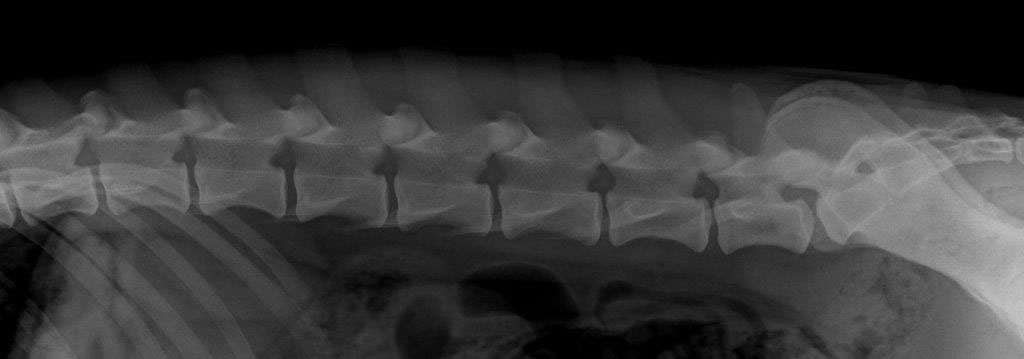

| Rug : | normaal, 7 wervels (foto) | |

| LTV : | Graad 1 (S1&S2 niet vergroeid) | |